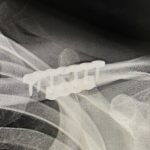

Background: The success of shoulder width narrowing by clavicle reduction osteotomies depends on stable plate and screw fixation. Holding the bones in place until the body starts to knit the two cut ends together requires them to be held in stable proximity for the first month after surgery. Such fixation success depends on having a Read More…